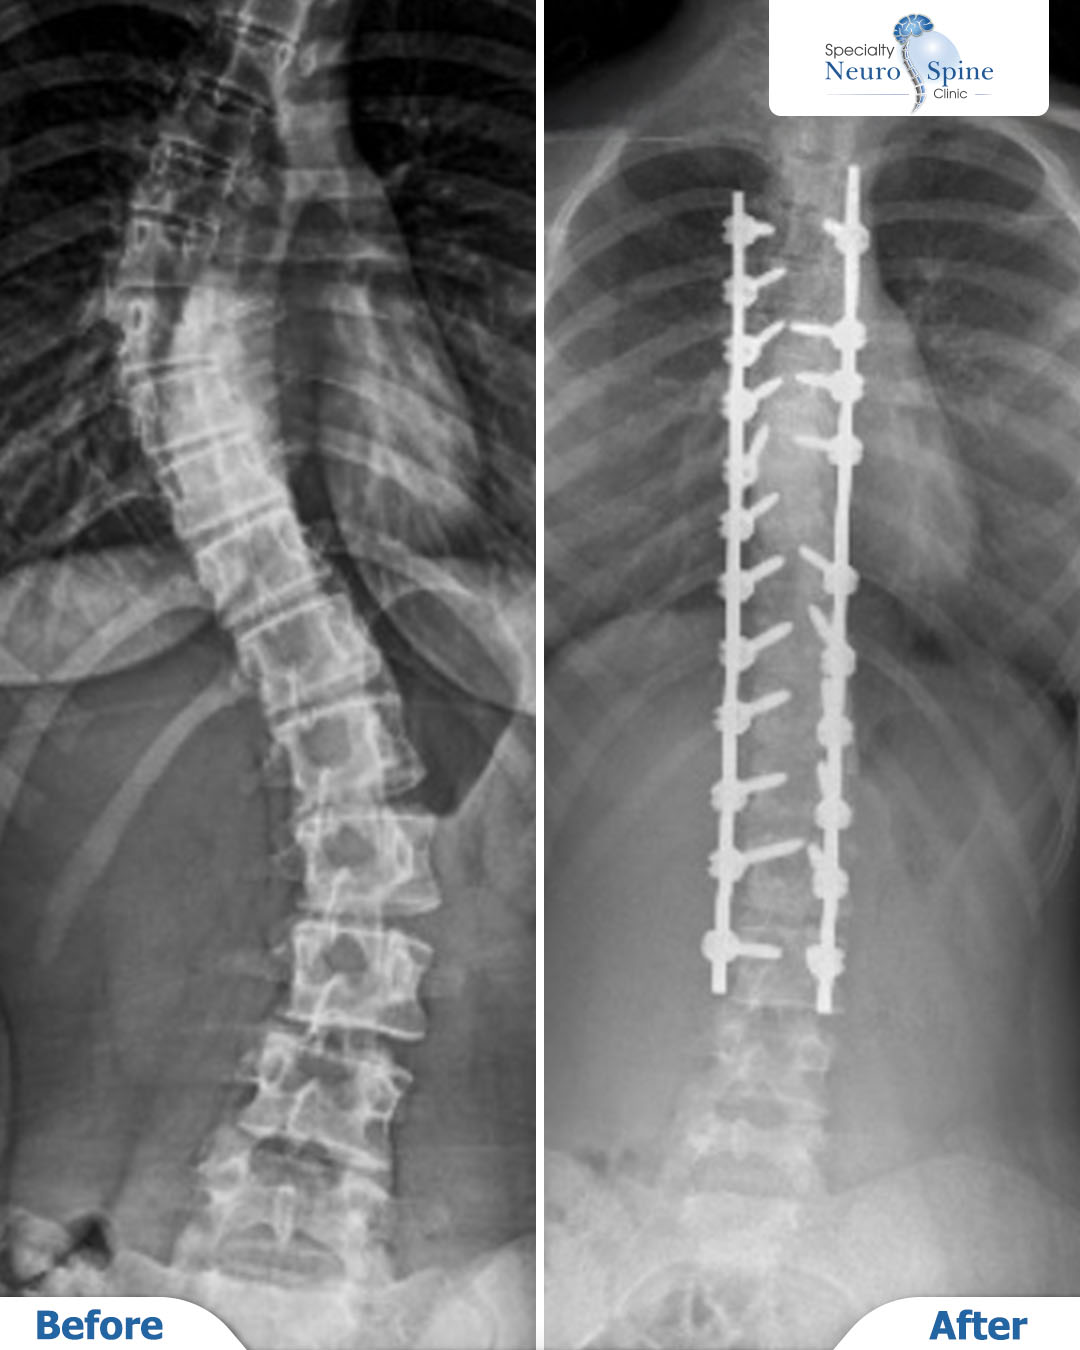

من زيارة مريضتنا الغالية مريم، 14 عاماً من الأردن، بعد شهر من عملية تصحيح انحراف العمود الفقري بالتدخل الجراحي المحدود.

بدأت المشي في اليوم التالي للعملية، وبعد شهر واحد فقط كانت قد عادت إلى ممارسة حياتها اليومية بشكل كامل.

رحلة قصيرة لكنها فارقة، تعكس أهمية التدخل في الوقت المناسب، والنتائج التي يحققها الدكتور فراس الحُسبان لمرضاه.